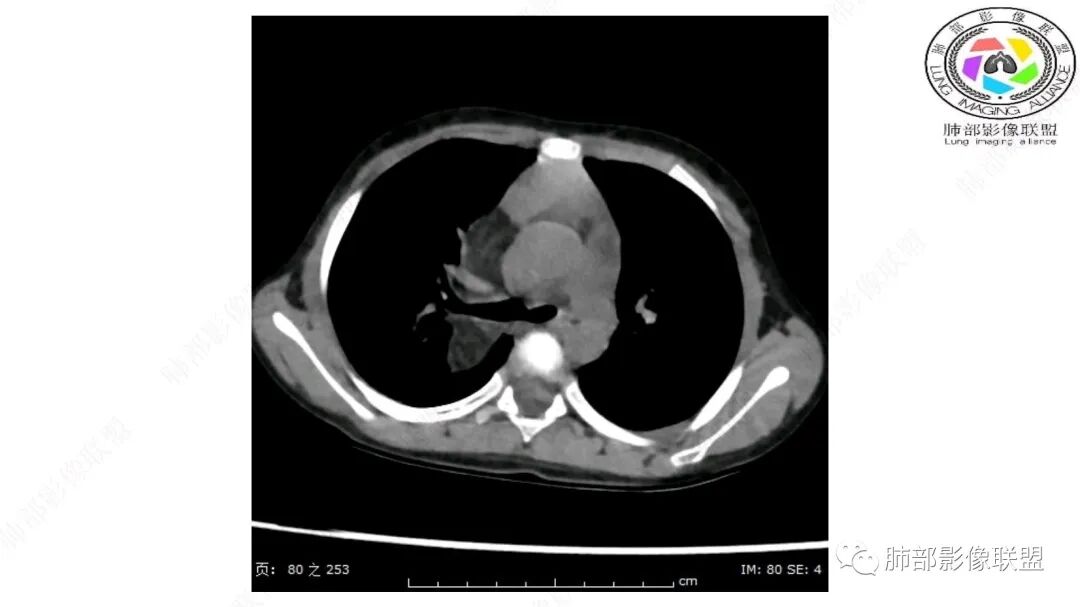

Coke with ice:

跨肺门,包绕肺血管分支,邻近肺组织受压肺不张。

可以看到造影剂进入的丛状结构

密度不均,非纯脂肪成分。斑片状密度略高区域有轻度填充式强化。

婴幼儿,病变较大,跨肺门,分叶,富含纤维或黏液、含成熟脂肪,破坏力弱或无,浸润性生长模式不明显,未见远处转移。

2.肺动脉穿行也许是肺内来源最重要支持点!